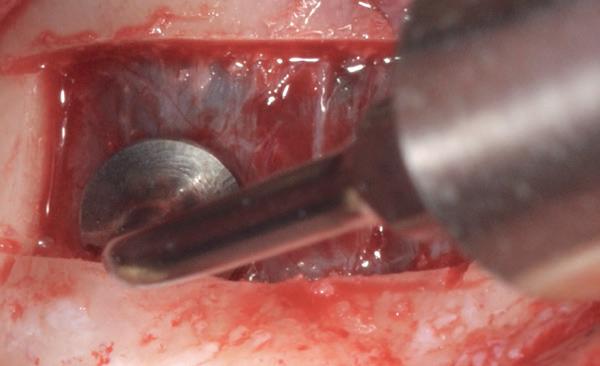

Verticaal botverlies & korte implantaten - De resorptie treedt soms overwegend verticaal op, waardoor de processus alveolaris geheel verdwijnt en er slechts een minimale hoeveelheid basaal/ residuaal bot overblijft. In de mandibula kan dit leiden tot een zeer lage kaak, met mediane kaakhoogtes tot nog maar 4-5 mm (potlood dikte!). Voorheen werd hier een transmandibulair implantaat geplaatst, omdat werd geanticipeerd op breuk [Powers et al, 1994], of werd gekozen voor het verticaal opbouwen van de mandibula: de klassieke absolute kaakverhoging. Tegenwoordig wordt het plaatsen van twee of vier korte implantaten met een lengte van slechts 4-8 mm beschouwd als een goed alternatief voor een augmentatie van de onderkaak (afbeelding 2). Dit scheelt aanmerkelijk in de belasting van de patiënt (minder ingrepen, geen narcose, kortere behandelduur, minimale morbiditeit) en levert goede resultaten op [Vazouras K et al, 2020; Telleman G, et al. 2013; Renouard F and Nisand D. 2006; Guljé F et al. 2012]

Horizontaal botverlies en mini-implantaten - Een geheel andere anatomische situatie ontstaat bij een meer horizontaal resorptiepatroon. Hierbij blijft de kaakhoogte vrijwel volledig intact, maar neemt de dikte van de processus alveolaris af tot een minimum van slechts enkele millimeters. Indien sprake is van een dergelijke zeer dunne processus alveolaris in de maxilla of mandibula, kan ervoor worden gekozen om gebruik te maken van mini-implantaten (implantaten met een diameter < 2.5 tot 3 mm, afbeeldingen 3a-b), als alternatief op een chirurgische kaakverbreding door middel van ‘buccal plating’ met een autoloog bottransplantaat. Het gebruik van mini-implantaten bespaart de patiënt pre-implantologische chirurgie, lange behandelduur, morbiditeit en de noodzaak tot herhaalde aanpassingen van de prothese. Door mini-implantaten flapless te plaatsen wordt de morbiditeit tot een minimum gereduceerd. Hiervoor is echter wel 3D-planning vooraf een vereiste alsook statische navigatie bij het plaatsen door middel van een dwingende boormal, vanwege de zeer geringe marges (zie casus, afbeeldingen 4a-q ). Een bijkomend voordeel van mini-implantaten is, dat ze uit één geheel bestaan en standaard zijn voorzien van

4a. Navigatie chirurgie met een dwingende boormal

4b. Na plaatsen wordt de boormal gefixeerd met ‘anchor pins’

4c. Voor mini-implantaten hoeft slechts één keer te worden geboord

4d. Uitnemen boormal na het ‘blind’ prepareren van het implantaatbed

een drukknopje. Hierdoor kan in een laatste levensfase eenvoudig nog een overkappingsprothese worden aangepast of vervangen, ook wanneer er geen aanvullende informatie meer beschikbaar is over het implantaatmerk, type en diameter. Mini-implantaten laten goede succes- en overlevingspercentages zien [Bidra en Almas 2013; Shatkin 2012; vanDoorne et al 2020; vanDoorne et al 2021]

voor alle implantaten

4e. Mini-implantaat (Southern Implants, ILZ12D), diameter 2.4 mm

4f. Flapless plaatsen van het 1e implantaat

4g. Door het genavigeerd prepareren is het plaatsen van de implantaten kinderlijk eenvoudig

4h. Direct postoperatief na flapless aanbrengen van 6 mini-implantaten